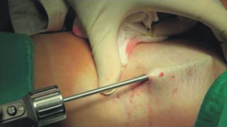

新式的手術方式則是利用螺旋刮刀或是借用抽脂的器械於腋下開1-2個小傷口利用刮除或抽吸的方式將頂漿腺體移除。雖然相較於傳統的手術無法百分之一百清除頂漿腺,讓異味百分百消失,但也可以去除約八九成。剩下殘留的味道可以間隔使用肉毒幹菌素的注射來補強。同時也由於傷口較小,只要做好適當的術後壓迫,傷口癒合及皮膚本身較不易出問題。由於術後建議包紮壓迫傷口,於春夏之際接受手術容易造成悶熱不舒服,所以此類的手術都建議於秋冬較不易出汗的天氣裡進行。

新式的弧臭手術